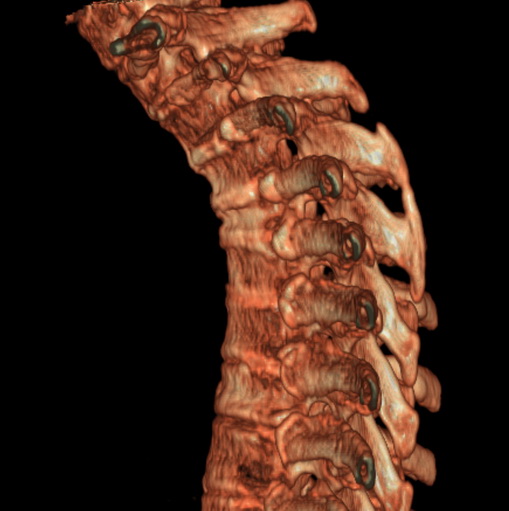

标题: CT25377:脊柱有无压缩骨折?

女、73、胸痛、胸闷3个月,无明显外伤病史,x线疑t4、t7陈旧压缩骨折,ct未经明显骨折,请问结论如何报?

老年女性病人,骨质稀疏,有些驼背,t4明显变扁,t7略变扁,椎体边缘无中断,骨小梁排列正常,无嵌插所致致密线。结合无明显外伤史,考虑老年骨质稀疏,慢性压缩改变,正如老年人骨质稀疏椎体呈双凹改变一样。我考虑报:老年骨质稀疏,t4、t7楔形变,脊柱曲度改变(驼背).敬请大家指教。

1)多个胸椎陈旧性压缩性骨折。2)胸椎普遍性骨质疏松。3)胸椎退行性改变。